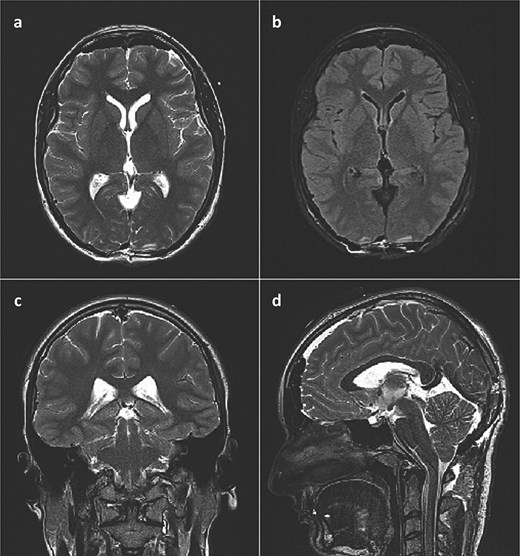

She was admitted to the hospital and an external ventricular drainage was placed in the right lateral ventricle for the treatment of hydrocephalus. The procedure was uneventful and, at that time, ameliorated her symptoms. Five days later, the patient was subjected to a surgical excision of the pineal gland cyst. She was operated on in a sitting position with her neck slightly flexed and head fixed rigidly with the Mayfield head clamp, using a SCIT approach in its standard fashion. Her postoperative recovery was uneventful, with the postoperative head CT scan and brain MRI showing no signs of hemorrhage or tumor residues (Fig. 3).

Postoperative brain MRI scan showing no residual tumor. (a) T2 weighted image, axial slice; (b) FLAIR image, axial slice; (c) T2 weighted image, coronal slice; (d) T2 weighted image (SPACE), sagittal slice).